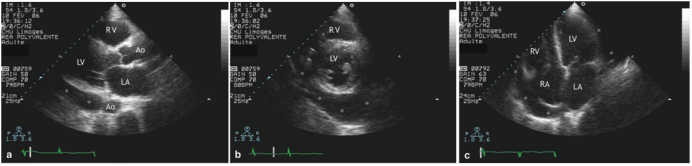

心包积液与胸腔积液的鉴别在临床中也存在一定困难, 一般我们在胸骨旁长轴进行鉴别: 胸腔积液的无回声区可延展至降主动脉后方, 且与心脏的结构关系并不密切; 心包积液通常在主动脉前方终止, 且与心脏的关系更为密切(图8)

图片

8  胸腔积液与心包积液的鉴别

通过该患者多切面超声图像分析:①胸骨旁长轴切面(图9a):于后心包区域可见无回声区,需鉴别心包积液与胸腔积液。从解剖定位看,无回声区在主动脉(Ao)前方或外部。②左室短轴切面(图9b):无回声区显示更清晰,其位于左室后方,与心室壁贴合关系不紧密。③剑突下切面(图9c):未探及明显心包积液征象(心包腔内无特征性无回声区)。④肺部超声(图9d):胸腔内明确探及无回声区(*号标识的区域)。结合前序切面的定位分析,可印证胸骨旁长轴的无回声区为胸腔积液,而非心包积液。

9  心包积液与胸腔积液的超声鉴别